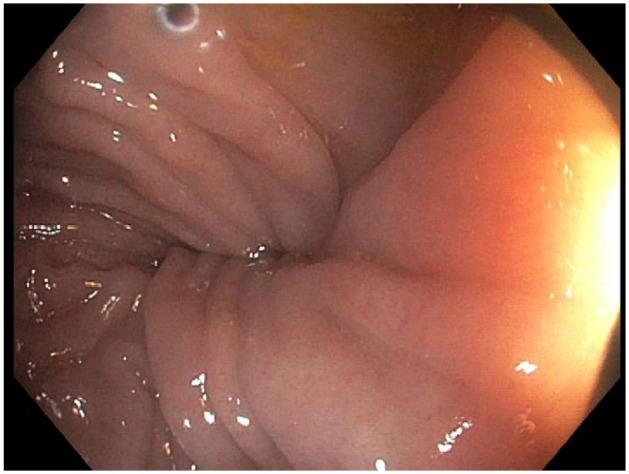

15岁男性乙状结肠扭转的内镜下复位术

Endoscopic Reduction of Sigmoid Volvulus in a 15-Year-Old Male.

Sigmoid volvulus is a well-recognized phenomenon in the elderly but rare in children. The proposed mechanism involves rotation of a redundant sigmoid loop around a narrow, elongated mesentery with subsequent vascular occlusion. The condition can be intermittent or may resolve spontaneously, complicating diagnosis. Early diagnosis is imperative to prevent ischemic complications including necrosis, perforation, and sepsis. Abdominal pain, abdominal distention, and vomiting are the most common presenting symptoms, however abdominal tenderness is uncommon. Colonic dilation is the most frequent finding on abdominal radiograph. Contrast enema reveals a "bird's beak" configuration of the twisted colon and moreover, is successful in reducing the majority of pediatric cases. If there is no evidence of bowel ischemia or perforation, endoscopic reduction has been proposed as first-line treatment for sigmoid volvulus, especially in children. We report the case of 15-year-old male in which endoscopic reduction of sigmoid volvulus was successful without complication.

摘要

乙状结肠扭转在老年人中是一种广为人知的现象,但在儿童中罕见。其推测机制包括一个冗长的乙状结肠袢围绕狭窄、细长的肠系膜旋转,随后发生血管闭塞。这种情况可以是间歇性的,也可能自行缓解,这使得诊断变得复杂。早期诊断对于预防包括坏死、穿孔和败血症在内的缺血性并发症至关重要。腹痛、腹胀和呕吐是最常见的症状表现,然而腹部压痛并不常见。结肠扩张是腹部X线片上最常见的表现。钡剂灌肠显示扭转结肠呈“鸟嘴”状,而且,大多数儿科病例通过钡剂灌肠复位成功。如果没有肠缺血或穿孔的证据,内镜复位已被提议作为乙状结肠扭转的一线治疗方法,尤其是在儿童中。我们报告了一例15岁男性患者,其乙状结肠扭转经内镜复位成功且无并发症。